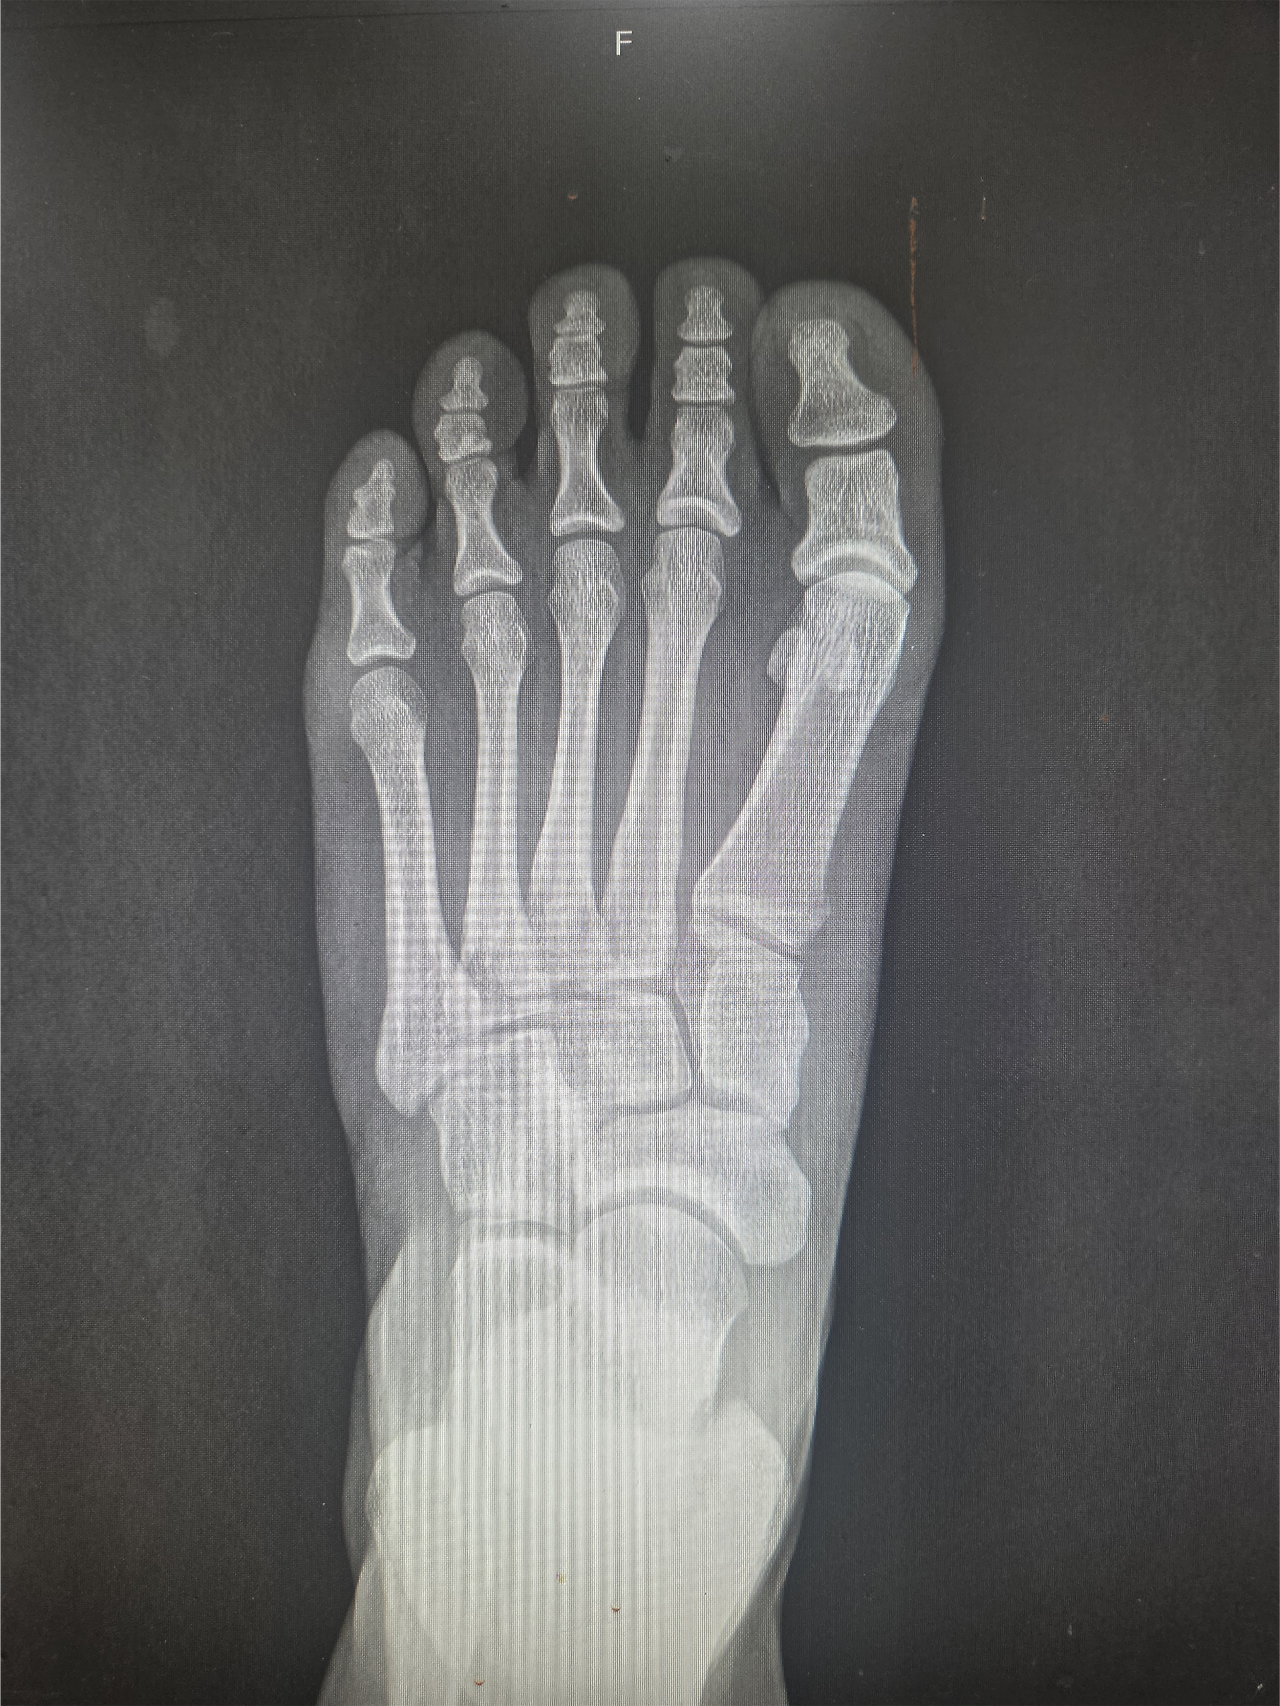

그가 처음 내 진료실을 찾은 것은 2024년 11월이었다. 당시 그는 이미 6개월 이상 엄지발가락 통증에 시달리며 여러 병원을 전전하던 상태였다. 깁스와 목발, 물리치료와 주사 치료까지 해볼 수 있는 건 다 해봤지만, 통증은 날카롭게 찢어지는 듯 심해졌고 보행조차 점차 어려워지고 있었다. 우선 시행한 X-ray 검사에서 통증 부위인 우측 종자골이 두 조각으로 나뉜 '이분 종자골' 형태가 확인되었다.

특이한 점이 있었다. 보통 이분 종자골은 80% 이상의 환자에서 양쪽 발 모두 관찰되는데, 이 환자는 유독 통증이 있는 우측에만 존재했다. 물론 한쪽만 이분 종자골인 경우도 드물지 않고, 환자의 직업 특성상 발에 충격이 잦아 '종자골염'일 가능성도 컸다.